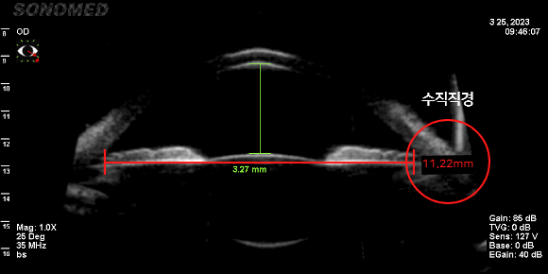

정확한 안구공간 측정

렌즈가 삽입될 공간이 충분한지 안구 공간 측정이 정확히 이루어져야 수술 가능 여부, 렌즈 사이즈,

렌즈 회전율을 최소화할 수 있는 렌즈 삽입 위치가 결정됩니다.

평균적으로 수직 직경이 수평 직경보다 길기 때문에 수직형 V-토릭 ICL은 넓은 공간에 여유 있는 사이즈의 렌즈가 삽입되어

렌즈 주변부의 접촉이 없어 렌즈삽입술의 부작용을 방어하고 안정성이 높습니다.

• 수평 안구 공간 측정 (11.01mm)

• 수평 안구 공간 측정 (11.22mm)

수직 직경 공간이 더 넓음